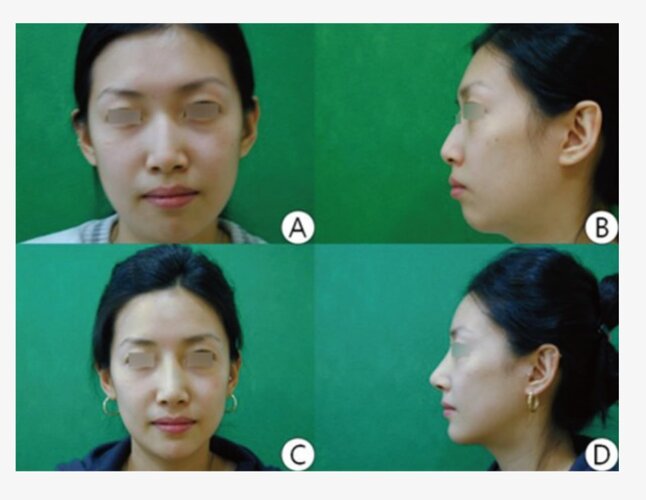

- The case below fits the criteria, the patients ANS and nose was fine in proportion to the rest of the face, but the maxilla sat almost vertical with little to none anterior facial depth. Advancing the lefort 2 block gave the missing anterior depth and transformed her frontal view.

Many "sunken" midfaces are caused more by a recessed ANS and paranasal area than by full maxillary retrusion. A correction of the paranasal region with an implant, graft, or a USO can often improve nasal projection, philtrum support, and overall facial harmony without needing extreme midface advancement. Lefort 2 should be used for severe anterior midface deficiency, not as a default when someone has midface retrusion.